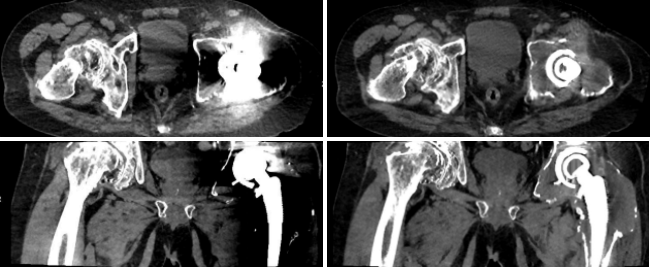

病例一 男,76歲, 髖關(guān)節(jié)置換術(shù)后翻新術(shù)前檢查

SEMAR OFF SEMAR ON

左側(cè)髖關(guān)節(jié)內(nèi)見(jiàn)置換物影,未使用SEMAR技術(shù)前見(jiàn)大片低密度偽影,周圍組織顯示不清。使用SEMAR技術(shù)去金屬偽影處理后,可見(jiàn)股骨頭及髖臼膨大,骨質(zhì)變薄,其內(nèi)見(jiàn)異常密度軟組織包繞置換物。

對(duì)于體內(nèi)金屬所產(chǎn)生的偽影,常規(guī)CT減輕其影響的辦法是:薄層掃描抑制其部分容積效應(yīng),選擇較高千伏值減其射線硬化影響等,但無(wú)法根本解決。所以目前術(shù)后檢查首選X線檢查,對(duì)CT與MR為檢查相對(duì)禁忌癥。

640層寬體探測(cè)器CT搭載了最新一代單能金屬偽影消除技術(shù),無(wú)需采用雙能采集,亦可在不知道病人是否有金屬偽影的前提下,后期進(jìn)行去金屬偽影重建。從而有效改善金屬物體和周圍組織的成像情況, 得到更加準(zhǔn)確的診斷結(jié)果。